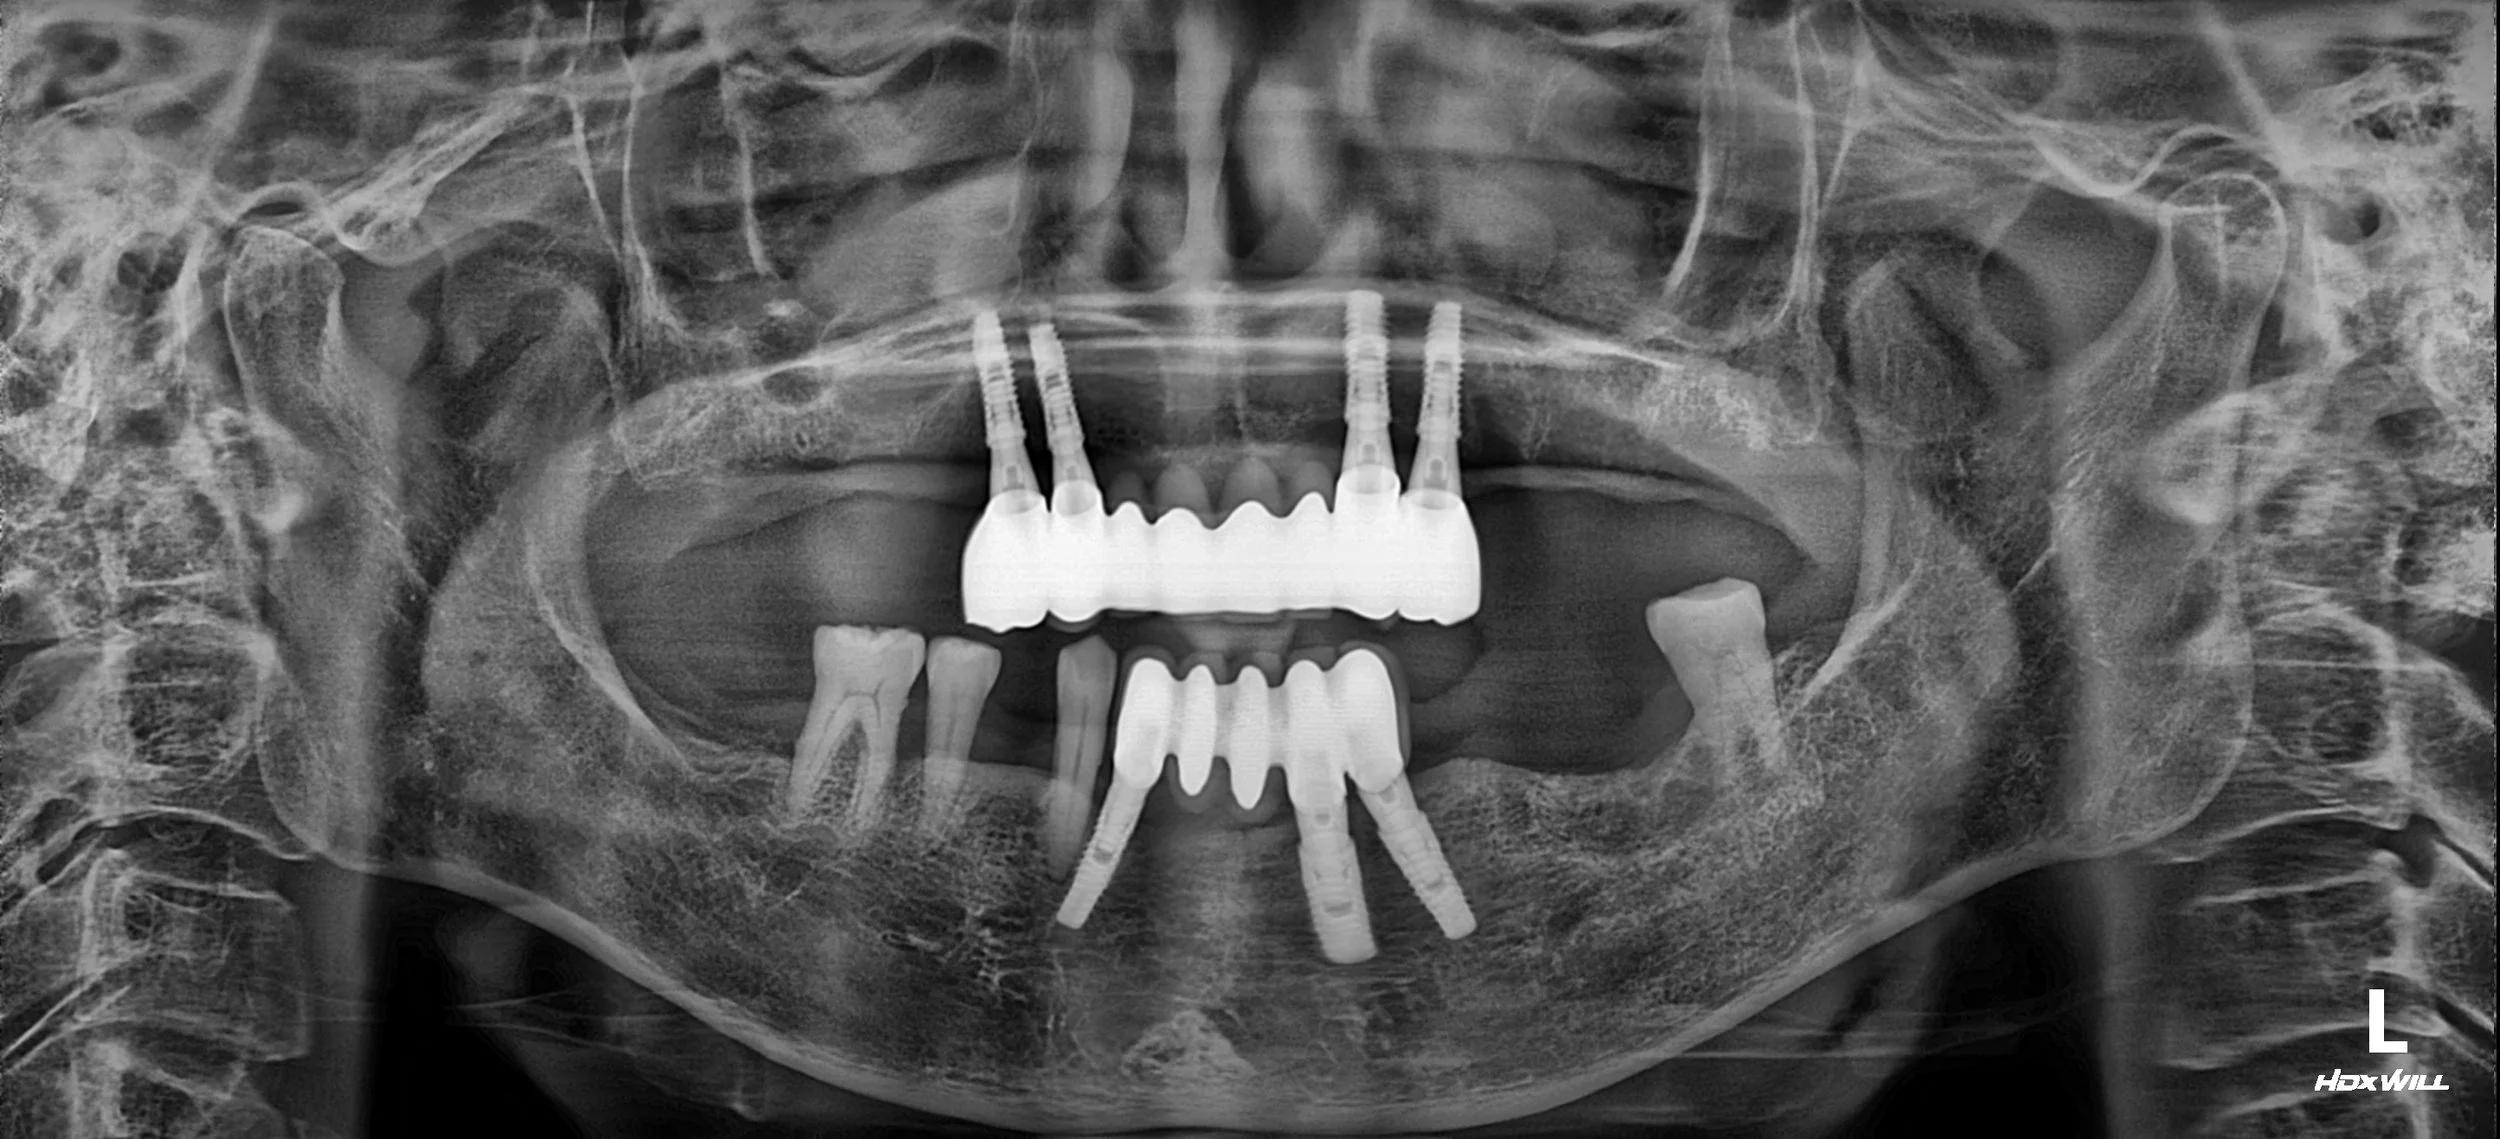

38. Comprehensive Full-Arch Reconstruction: Reversing the Domino Effect of Tooth Loss

Management of Generalized Severe Periodontitis and Posterior Bite Collapse in a Female Patient in her 60s. A Systematic Approach to VDO Recovery and Strategic Esthetic Rejuvenation.